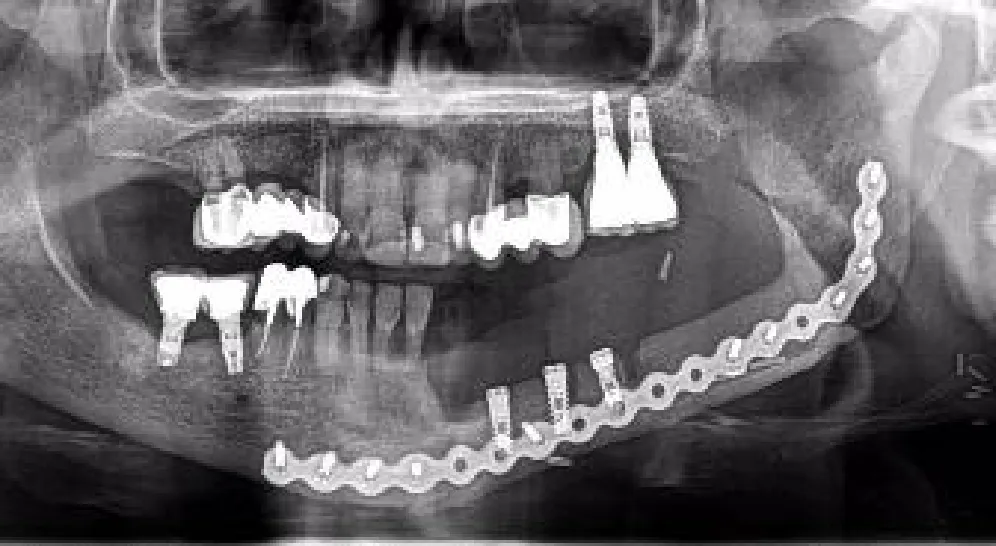

Therefore, VSP surgical translation was individualized in each patient. For example in two of them presenting almost an ideal restored anatomy, or when treating a non-reconstructed jaw, we applied a close transmucosal surgical technique with conventional static-guided surgery concept. In one patient, the mandible was treated with dCAIS and the maxilla with sCAIS. In four patients, we mixed both concepts in the same jaw, starting with a half-guided sCAIS, drilling with the static guide and then placing the implant with dynamic navigation.

On the other hand, open dynamic image-guided navigation techniques enable real-time surgical tool tracking and visualization with respect to surrounding anatomical structures, allowing the surgeon to accurately place the implant on the position defined during preoperative virtual planning. The surgeon’s perception of the drilling sequence and implant placement is not affected by a splint. There is no need for a specific set of drills or instruments and can be used in almost all patients, even in cases with limited mouth opening. Kalaivani et al. (13) stated that the major value of the dynamic design is the ability to adjust the planned implant positioning intraoperatively.

dCAIS tracking depends on the registration procedure. Errors in that step could be detected and corrected with continuous recalibration paying attention to reference fixation and position stability. Nevertheless, there are some limitations to evaluate since the registration process is technically sensitive and requires time. In addition, the surgeons need a steep learning curve and the cost of the equipment is high (41). Sun et al. (42) reported that the learning curve plateau is not reached until the surgeon has placed at least 15 dental implants with these systems. Our group created a workflow based on open software, avoiding extra costs, and included laboratory practice with biomodels to reduce the learning curve.

dCAIS in healthy non-oncological case results are excellent, and similar to the sCAIS, Yimarj et al. (19) reported a 1.24-mm crestal insertion error, 1.58-mm apical mismatch, and 3.78° angular deviation. In another systematic review and meta-analysis, Wei et al. (17) reported that the average global platform deviation, global apical deviation, and angular deviation were 1.02 mm, 1.33 mm, and 3.59°, respectively. Our subgroup of five patients, 30 implants, placed by means of a splint-based registration dynamic navigation technique yielded values of 1.52 mm, 2.49 mm, and 8°, respectively, slightly higher than in non-oncological patients.

Our workflow shares the best capabilities from both methods. Assuming that the surgical template is difficult to use alone in anatomically altered reconstructed oncologic patients and that dynamic navigation information allows intraoperative real-time modifications, we combine both techniques. The rigid tooth-supported acrylic 3D-printed splint provides a stable platform for patient registration and optical marker display. It also holds all the information for guided surgery and the cylinders for static drilling. In our last five patients, we placed the tip of the drill inside the cylinder using dynamic navigation to find the virtually planned crestal insertion point and the best handpiece axis orientation before starting to drill. The main difference with a conventional static drilling technique is that we have a certain degree of freedom within the guiding 5.2-mm-diameter tube, to slightly change the drill insertion point and axis as suggested by the intraoperative dynamic navigation display in order to match the virtual surgical plan. With this combined approach, our results in the last three oncologic patients resemble those achieved in healthy non-oncological patients.

In many implants, we noticed an intraoperative mismatch in the crestal insertion point between the static surgical guide and the dynamic navigation. We give more credit to the position provided by the navigation technique, and the postoperative implant position analysis reveals that dynamic navigation based on a stable splint offers superior accuracy to translate the virtual surgical planning into the operating room (Figure 9).